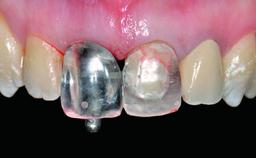

Replacement of an Upper Right Central Incisor with Root Resorption: Ridge Preservation, Early Placement of an RC Bone Level Implant

Abutment Type CAD/CAM

Prosthesis Type FDP